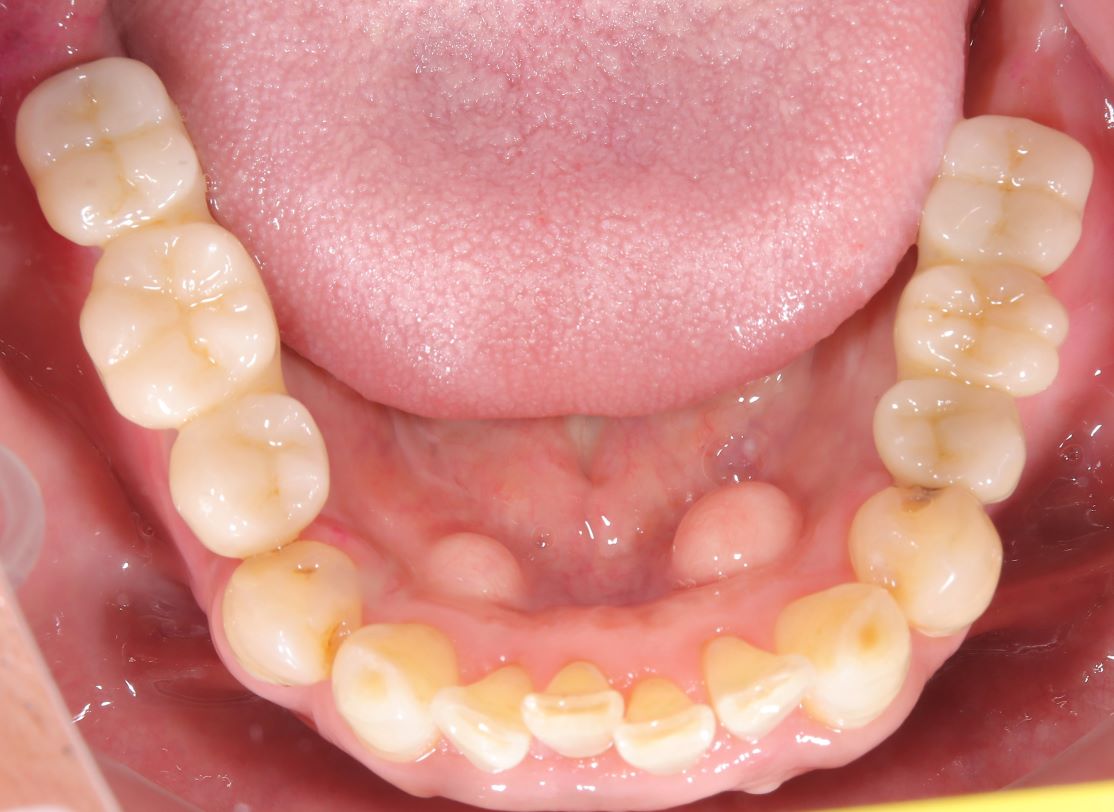

case 01.

BEFORE

AFTER

健康な歯を削ることに抵抗があり、より歯を長く保たせる治療を希望し来院された。

(リスク)